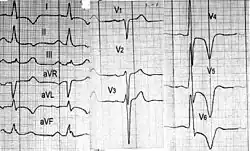

- Электрокардиография — никогда не бывает нормальной и поэтому является удобным методом скрининга. Обнаруживают признаки увеличения левого желудочка и левого предсердия. Возможны также признаки увеличения правого желудочка. Особенно характерны глубокие отрицательные зубцы Т различных локализаций, глубокие зубцы Q (часто в области перегородки). Выявляют различные нарушения ритма и проводимости.